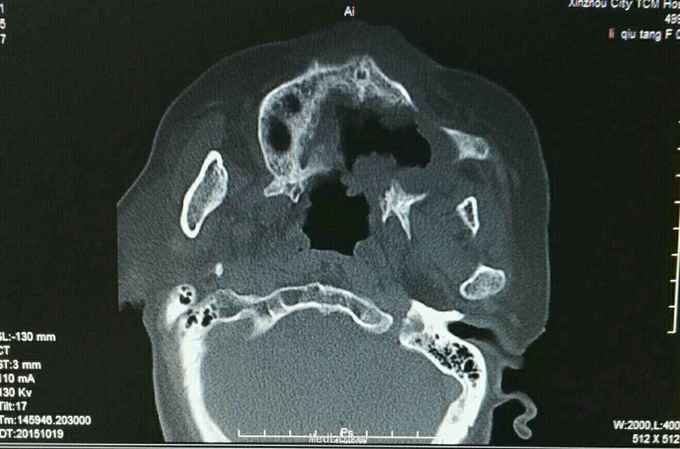

诊断:左上牙龈癌术后复发 治疗:2015.10.21CT引导下行碘125粒子植入术,图为术前定位

肿瘤的治疗应该多元化,该患者属于牙龈癌术后复发,患者不接受放化疗,遂予以碘125粒子植入术,手术成功,嘱患者术后45天返院复诊。